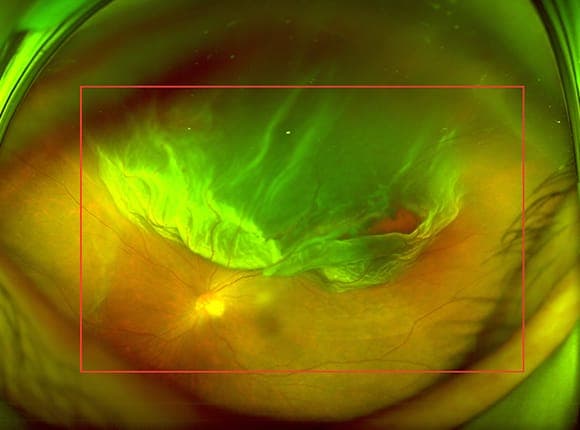

안구 내벽에 벽지처럼 붙어있어야 할 망막이 떨어져 나가는 질환입니다. 망막이 들뜨게 되면 영양 공급이 차단되어 시세포가 빠르게 손상되며, 방치할 경우 영구적인 실명으로 이어질 수 있는 안과적 응급 상황입니다.